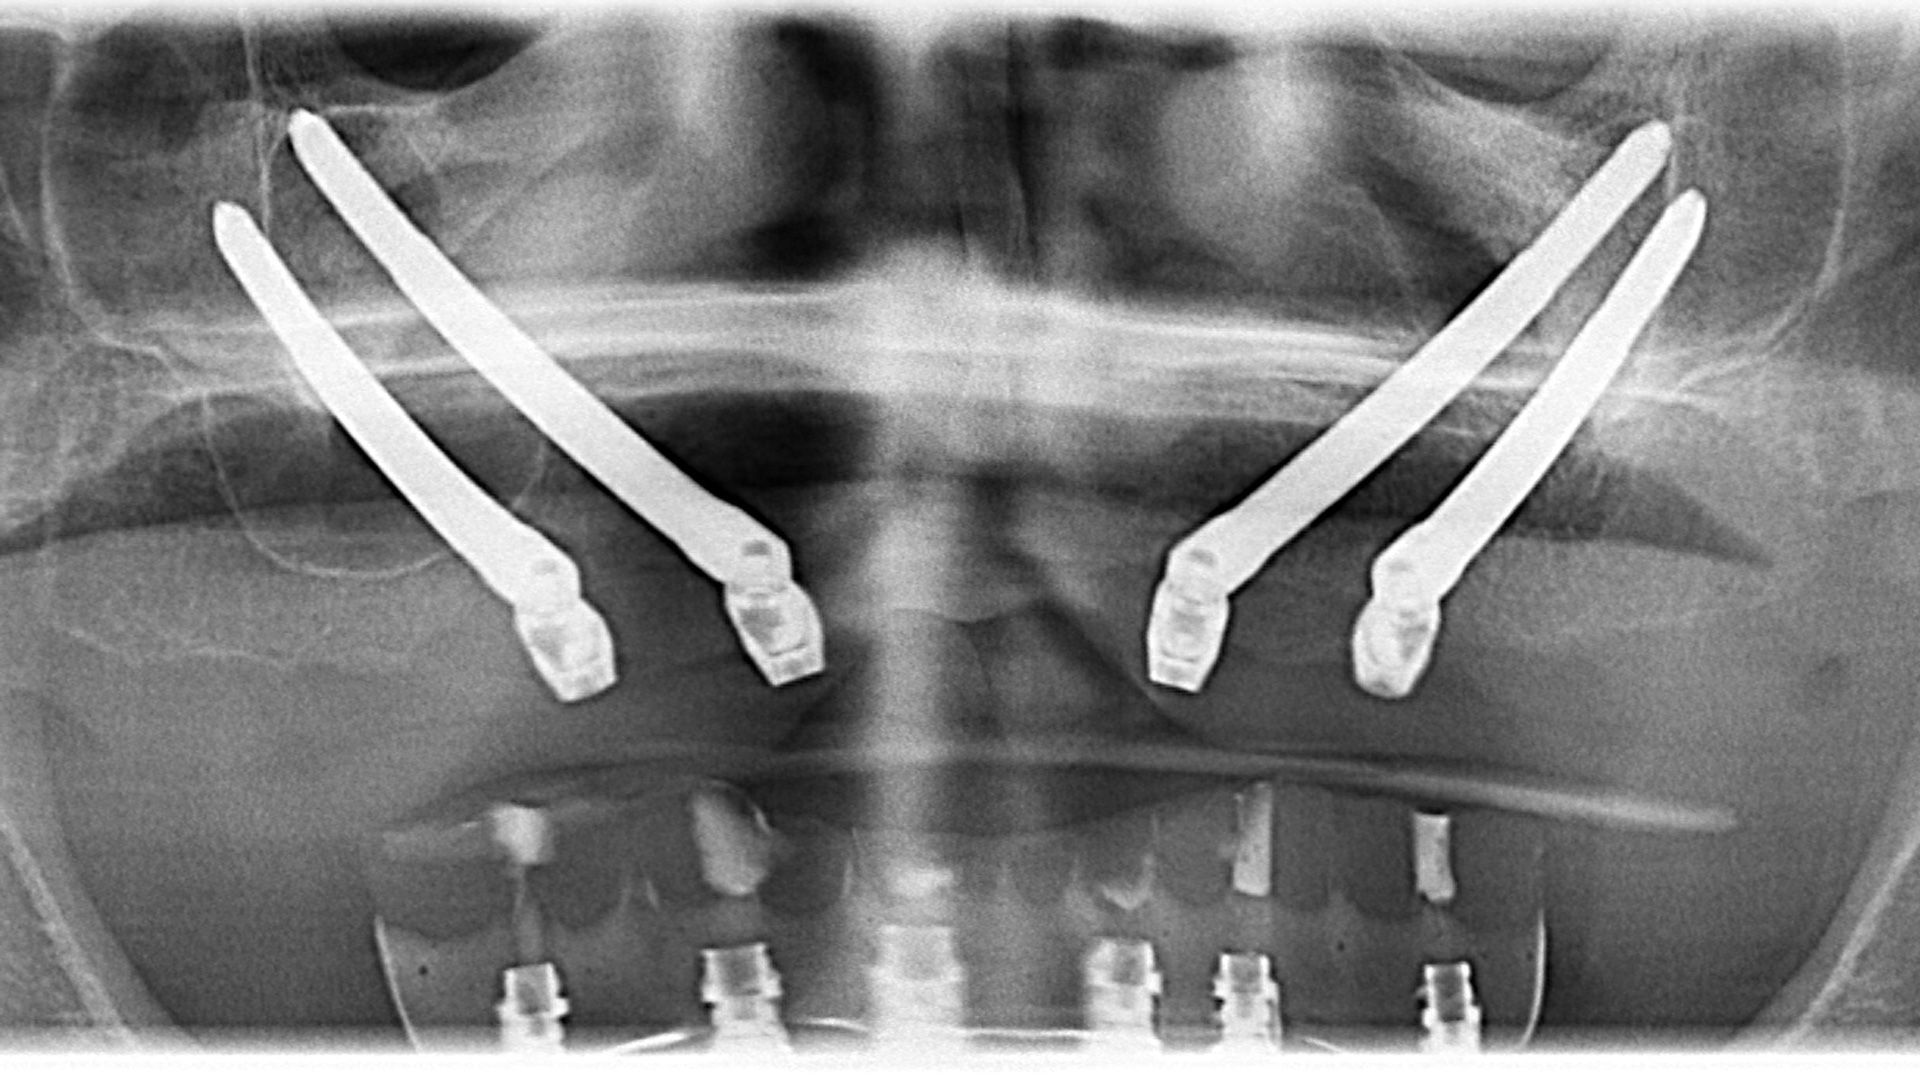

impianti classici – oggi per voi esiste una soluzione! Con l’aiuto degli impianti zigomatici vi possiamo offrire una soluzione fissa su 4 impianti. La differenza tra un

all-on-4 zigomatico e un

all-on-4 classico sta nella lunghezza degli impianti, nella direzione di innesto e nella posizione degli impianti. Mentre gli impianti classici si innestano parallelamente al seno mascellare e nella massa ossea frontale della mascella, gli

impianti zigomatici si innestano nell’osso zigomatico e in alcuni casi anche attraverso il seno mascellare. Gli

impianti zigomatici sono fatti in titanio, sono lunghi 30-60 mm in dipendenza dal caso clinico del paziente. L’operazione si svolge in anestesia locale, se necessario in sedazione coscente supervionata da un anestesiologo, ed è eseguita da un chirurgo maxillo facciale assistito da un chirurgo orale. Se per anni avete patito a causa di una totale mancanza di denti e avete sofferto a causa della protesi mobile, questo protocollo implantologico può essere la vostra ultima spiaggia.